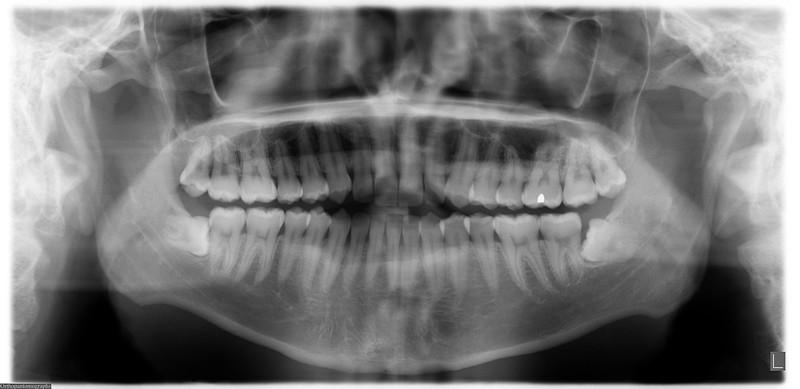

Стоматологические Исследования: Рентген Инвагинации Зубов